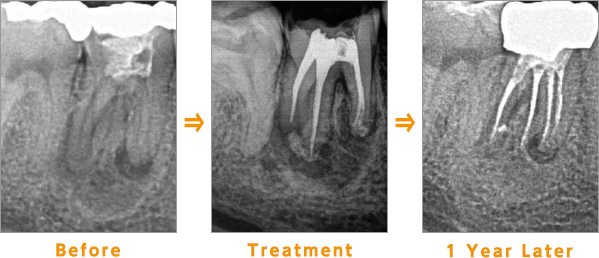

根管治療

根管治療には、虫歯が神経まで進行した場合に神経を取って治す治療と、なんらかの原因で根の尖端に膿が溜まった根管を除去する治療の2種類があります。

当院の根管治療は、ニッケルチタンファイルを使用し、効率良く根管内を綺麗にしています。

Before:根管の先に膿が溜まり、黒く(透過像)なっています。

Treatment:根管内の感染を起こした組織を除去し、薬剤を填入します。

1 year later:黒いところは白くなり、骨が再生していることを示しています。